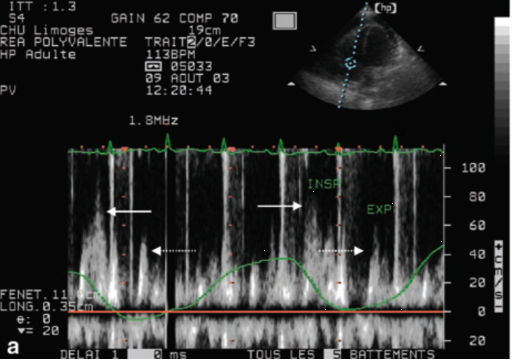

通过组织多普勒频谱分析也可以识别心包压塞。因为在生理状态下,左心室每搏量(SV)在吸气相轻微下降、呼气相轻微增加,右心室SV与之相反。正常情况下SV在吸气-呼气相差异较小;如果SV差异性增大,则提示心包压塞。在心包压塞的患者中,二尖瓣/三尖瓣流速在吸气相与呼气相差异度增大,表现为二尖瓣E波峰值流速在吸气时下降率≥25%;而跨三尖瓣流速增加≥40%。

如图10和图11所示:基于二尖瓣及三尖瓣血流频谱分析心包压塞的血流动力学特征:①二尖瓣血流频谱(图10):呼气相二尖瓣峰值流速约60 cm/s,吸气相降至约40 cm/s。二尖瓣峰值速度变异率=(60-40)/60×100%≈33%。当二尖瓣血流呼吸变异率>25%时,提示存在心包压塞。②三尖瓣血流频谱(图11):吸气相三尖瓣峰值流速约为80 cm/s,呼气相约为40 cm/s。三尖瓣峰值流速变异率=(80-40)/80×100%=50%。当三尖瓣流速增加≥40%,提示存在心包压塞。

图片

10  二尖瓣血流频谱

11  三尖瓣血流频谱